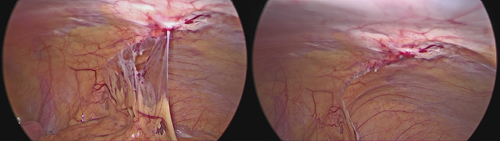

초음파검사상 난소에 혹이 발견되었고, 복강경 검사에서 '자궁내막증' 진단을 받았다. 수술로 혹을 제거하고 골반유착을 해결한 후로 생리통은 없어졌고, 현재 재발방지를 위해 약물치료를 시행하며 별다른 불편함 없이 잘 지내고 있다.

하지만 최종 확진은 복강경 검사를 해야 한다. 치료는 약물치료와 수술적 치료가 있으며 두 가지를 함께 시행할 수도 있다. 특히 난소낭종이 생기는 등 중증의 자궁내막증은 수술 후 재발방지를 위해 약물치료를 3~6개월 정도 시행하는 것이 좋다.

자궁내막증에 대한 일차적 예방은 현실적으로 어렵지만, 병의 예방과 합병증 발생을 줄이는 방법으로 조기진단을 들 수 있겠다. 증상이 있을시 복강경 검사를 통해 조기 진단하고 적절한 수술과 약물요법을 통해 병의 진행을 막는 것이 필수적이다.